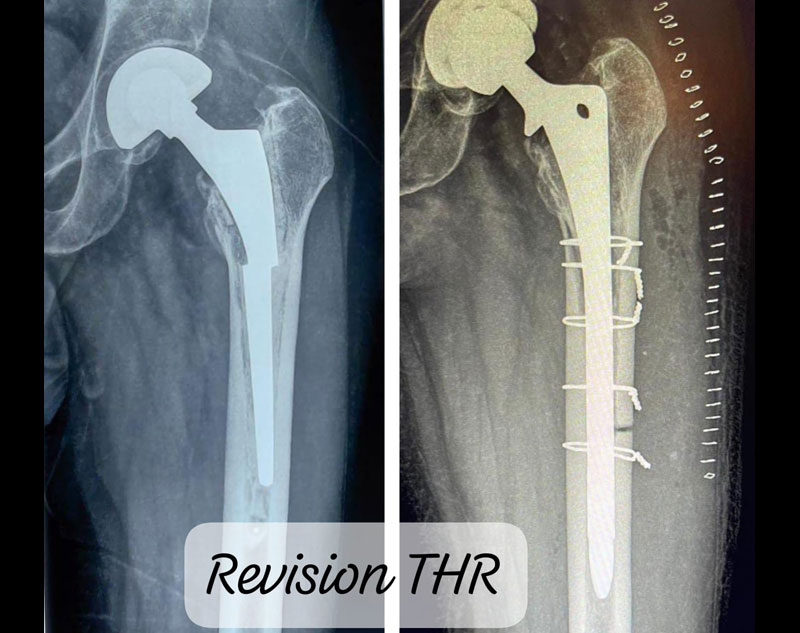

Revision hip replacement is a more complex surgery performed to replace or repair a hip prosthesis that has failed or worn out over time. It is necessary when the initial hip replacement no longer functions properly due to wear, infection, loosening, or other complications.